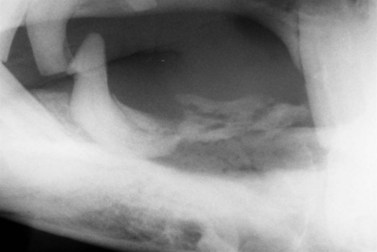

Fig. 9.11 Oblique radiographic image showing mandibular sequestrum.